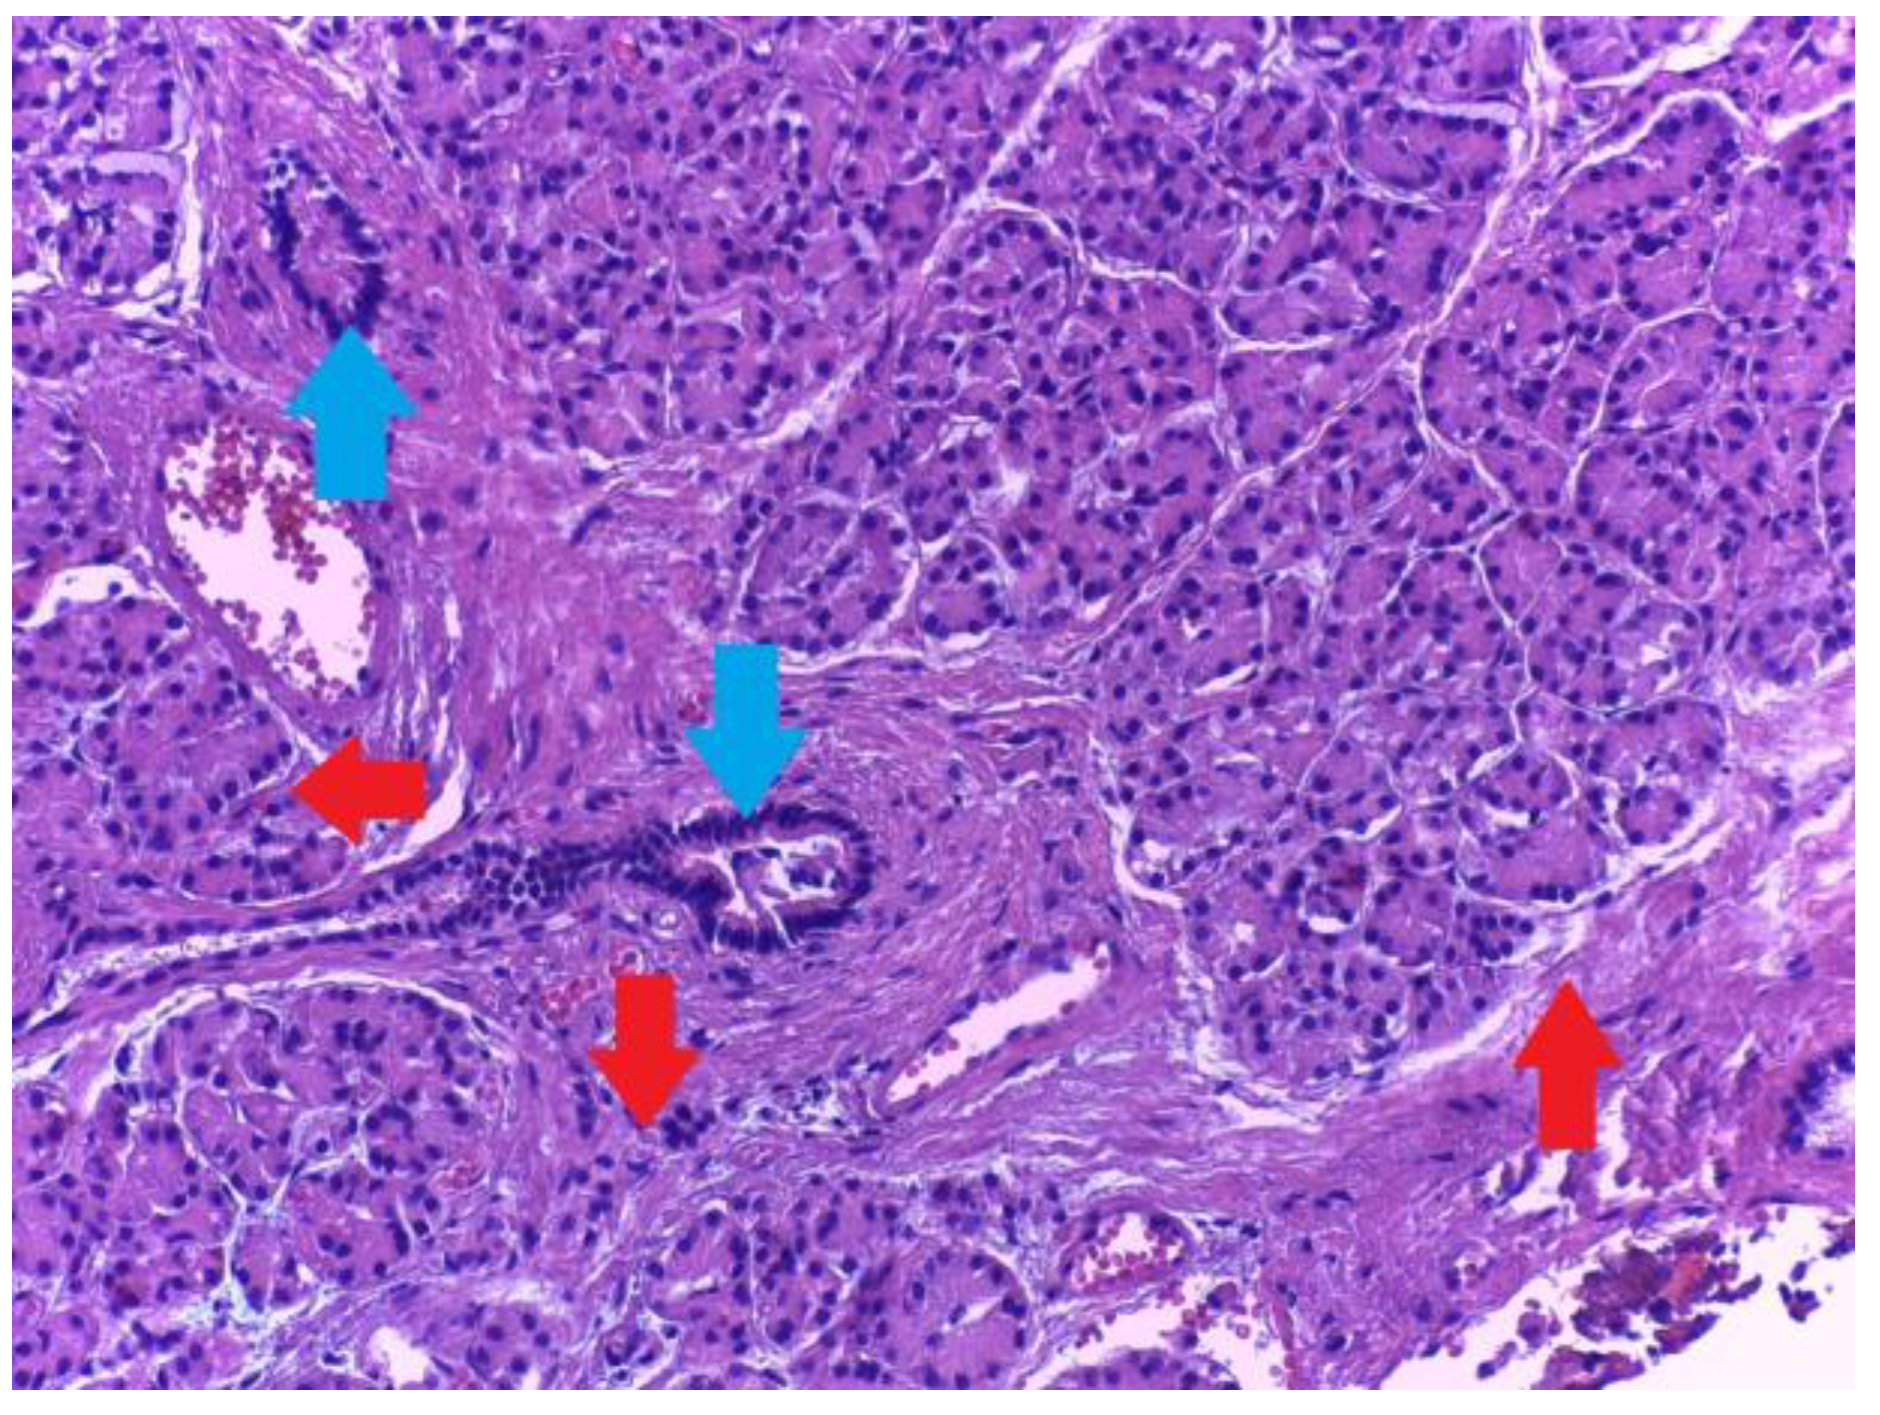

2.1. Type 1

2.2. Type 2

2.3. Type 3